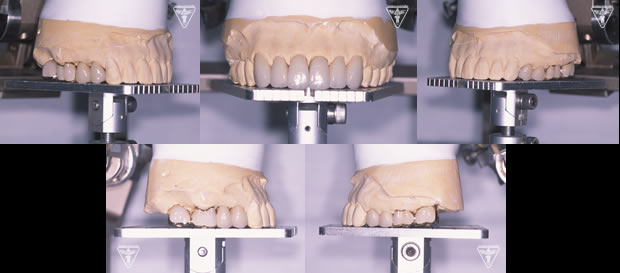

CTによるインプラント埋入位置の評価

SHILLA・Systemによる咬合平面・歯列弓の設定